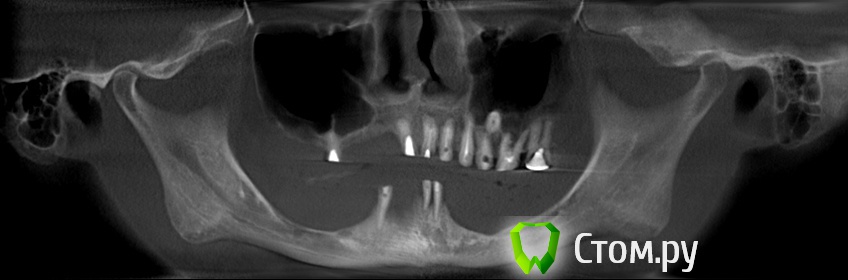

Игорь Пеликан Опубликовано 19 января, 2014 Поделиться Опубликовано 19 января, 2014 Прошу поделиться своими мыслями по поводу хирургической реабилитации(костная пластика) девушки 35 лет,все это покрыто двумя сьемниками.Верх-2 сектор оставляем,в 1 секторе синус,3D.Низ-закапываются сомнения в васкуляризации графта в дистальных отделах, 3D или репозиция,не хочется воспользоваться только междументальным расстоянием? Ссылка на комментарий

АнтонТЛТ Опубликовано 19 января, 2014 Поделиться Опубликовано 19 января, 2014 (изменено) Зд внизу не прокатит. Либо нерв двигать, либо в передний отдел вкручиваться Изменено 19 января, 2014 пользователем АнтонТЛТ 1 Ссылка на комментарий

АнтонТЛТ Опубликовано 19 января, 2014 Поделиться Опубликовано 19 января, 2014 Хотя нерв как мне кажется особо некуда двигать Ссылка на комментарий

Mane Опубликовано 19 января, 2014 Поделиться Опубликовано 19 января, 2014 репозиция нерва. установка имплантатов. далее нерв укладываете латерально. посмотреть бы еще несколько срезов от 36 до 46 Ссылка на комментарий

Игорь Пеликан Опубликовано 19 января, 2014 Автор Поделиться Опубликовано 19 января, 2014 репозиция нерва. установка имплантатов. далее нерв укладываете латерально. посмотреть бы еще несколько срезов от 36 до 46 Репозицию думаю не захочет,и стоит ли игра свечь,красоты и так не будет,а функцию можно и на междументальном сделать,каркас потолще и подвесить. Ссылка на комментарий

Игорь Пеликан Опубликовано 19 января, 2014 Автор Поделиться Опубликовано 19 января, 2014 Зд внизу не прокатит. Либо нера двигать, либо в передний отдел вкручиватьсяАргументируйте пожалуйста почему 3д не прокатит? Ссылка на комментарий

АнтонТЛТ Опубликовано 19 января, 2014 Поделиться Опубликовано 19 января, 2014 Дистально костных пик нет Ссылка на комментарий

АнтонТЛТ Опубликовано 19 января, 2014 Поделиться Опубликовано 19 января, 2014 Можно, но будет ли в данном случае прирост на нужную высоту или будет просто операция ради операции?В данном случае поставил бы в передний отдел без дополнительных костных пластик и переносов нерва. 1 Ссылка на комментарий

Игорь Пеликан Опубликовано 19 января, 2014 Автор Поделиться Опубликовано 19 января, 2014 Дистально костных пик нетзеленая линия на панорамнике проходит как раз таки по костным пикам,прирост все таки возможен? Ссылка на комментарий

АнтонТЛТ Опубликовано 19 января, 2014 Поделиться Опубликовано 19 января, 2014 (изменено) Дистально ветвь нижней челюсти, а не пики альвеолярного отростка. На такую высоту за один раз не поднять (если делать 3д) Изменено 19 января, 2014 пользователем АнтонТЛТ Ссылка на комментарий